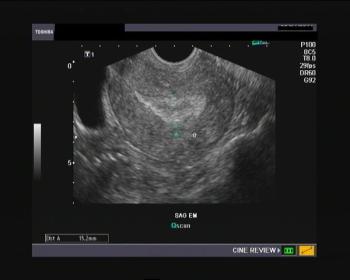

PCOS: An Epidemic • An epidemic in developing countries (ED & PCOS!!!). • About 20% of reproductive age women demostrate the ultrasound picture of polycystic ovaries. • About 5-10% have clinical or biochemical signs of Anovulation and androgen excess. (These date were collected prior to Rotterdam diagnostic consensus).